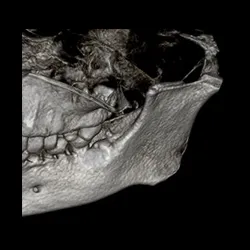

Case 1